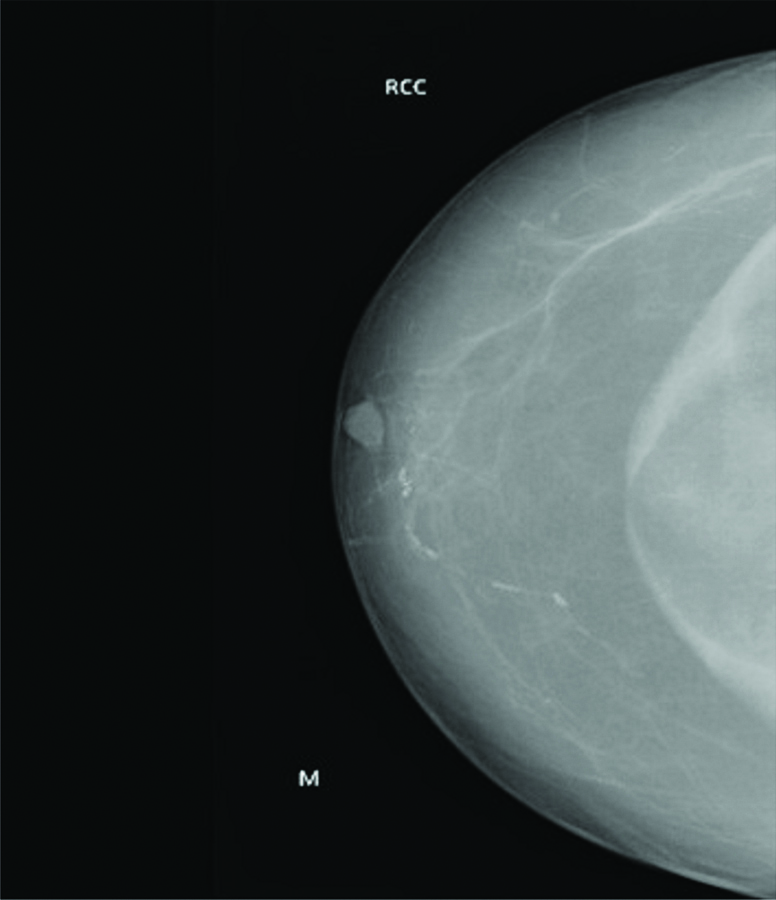

RCC (Right Craniocaudal) view of mammogram with radiopaque lesion with linear striation in the centre.

A mammogram was done which revealed large radiopaque lesion noted in the retro glandular region with in the pectoralis major muscles with lucent linear striation in the centre [Table/Fig-1,2], Correlated sonomammography showed a large hyperechoic lesion in retromammary region, within the pectoralis major muscle [Table/Fig-3], On Doppler study, no evidence of vascularity was noted. An ultrasound guided FNAC done, showed adipocyte which was suggestive of a lipoma.